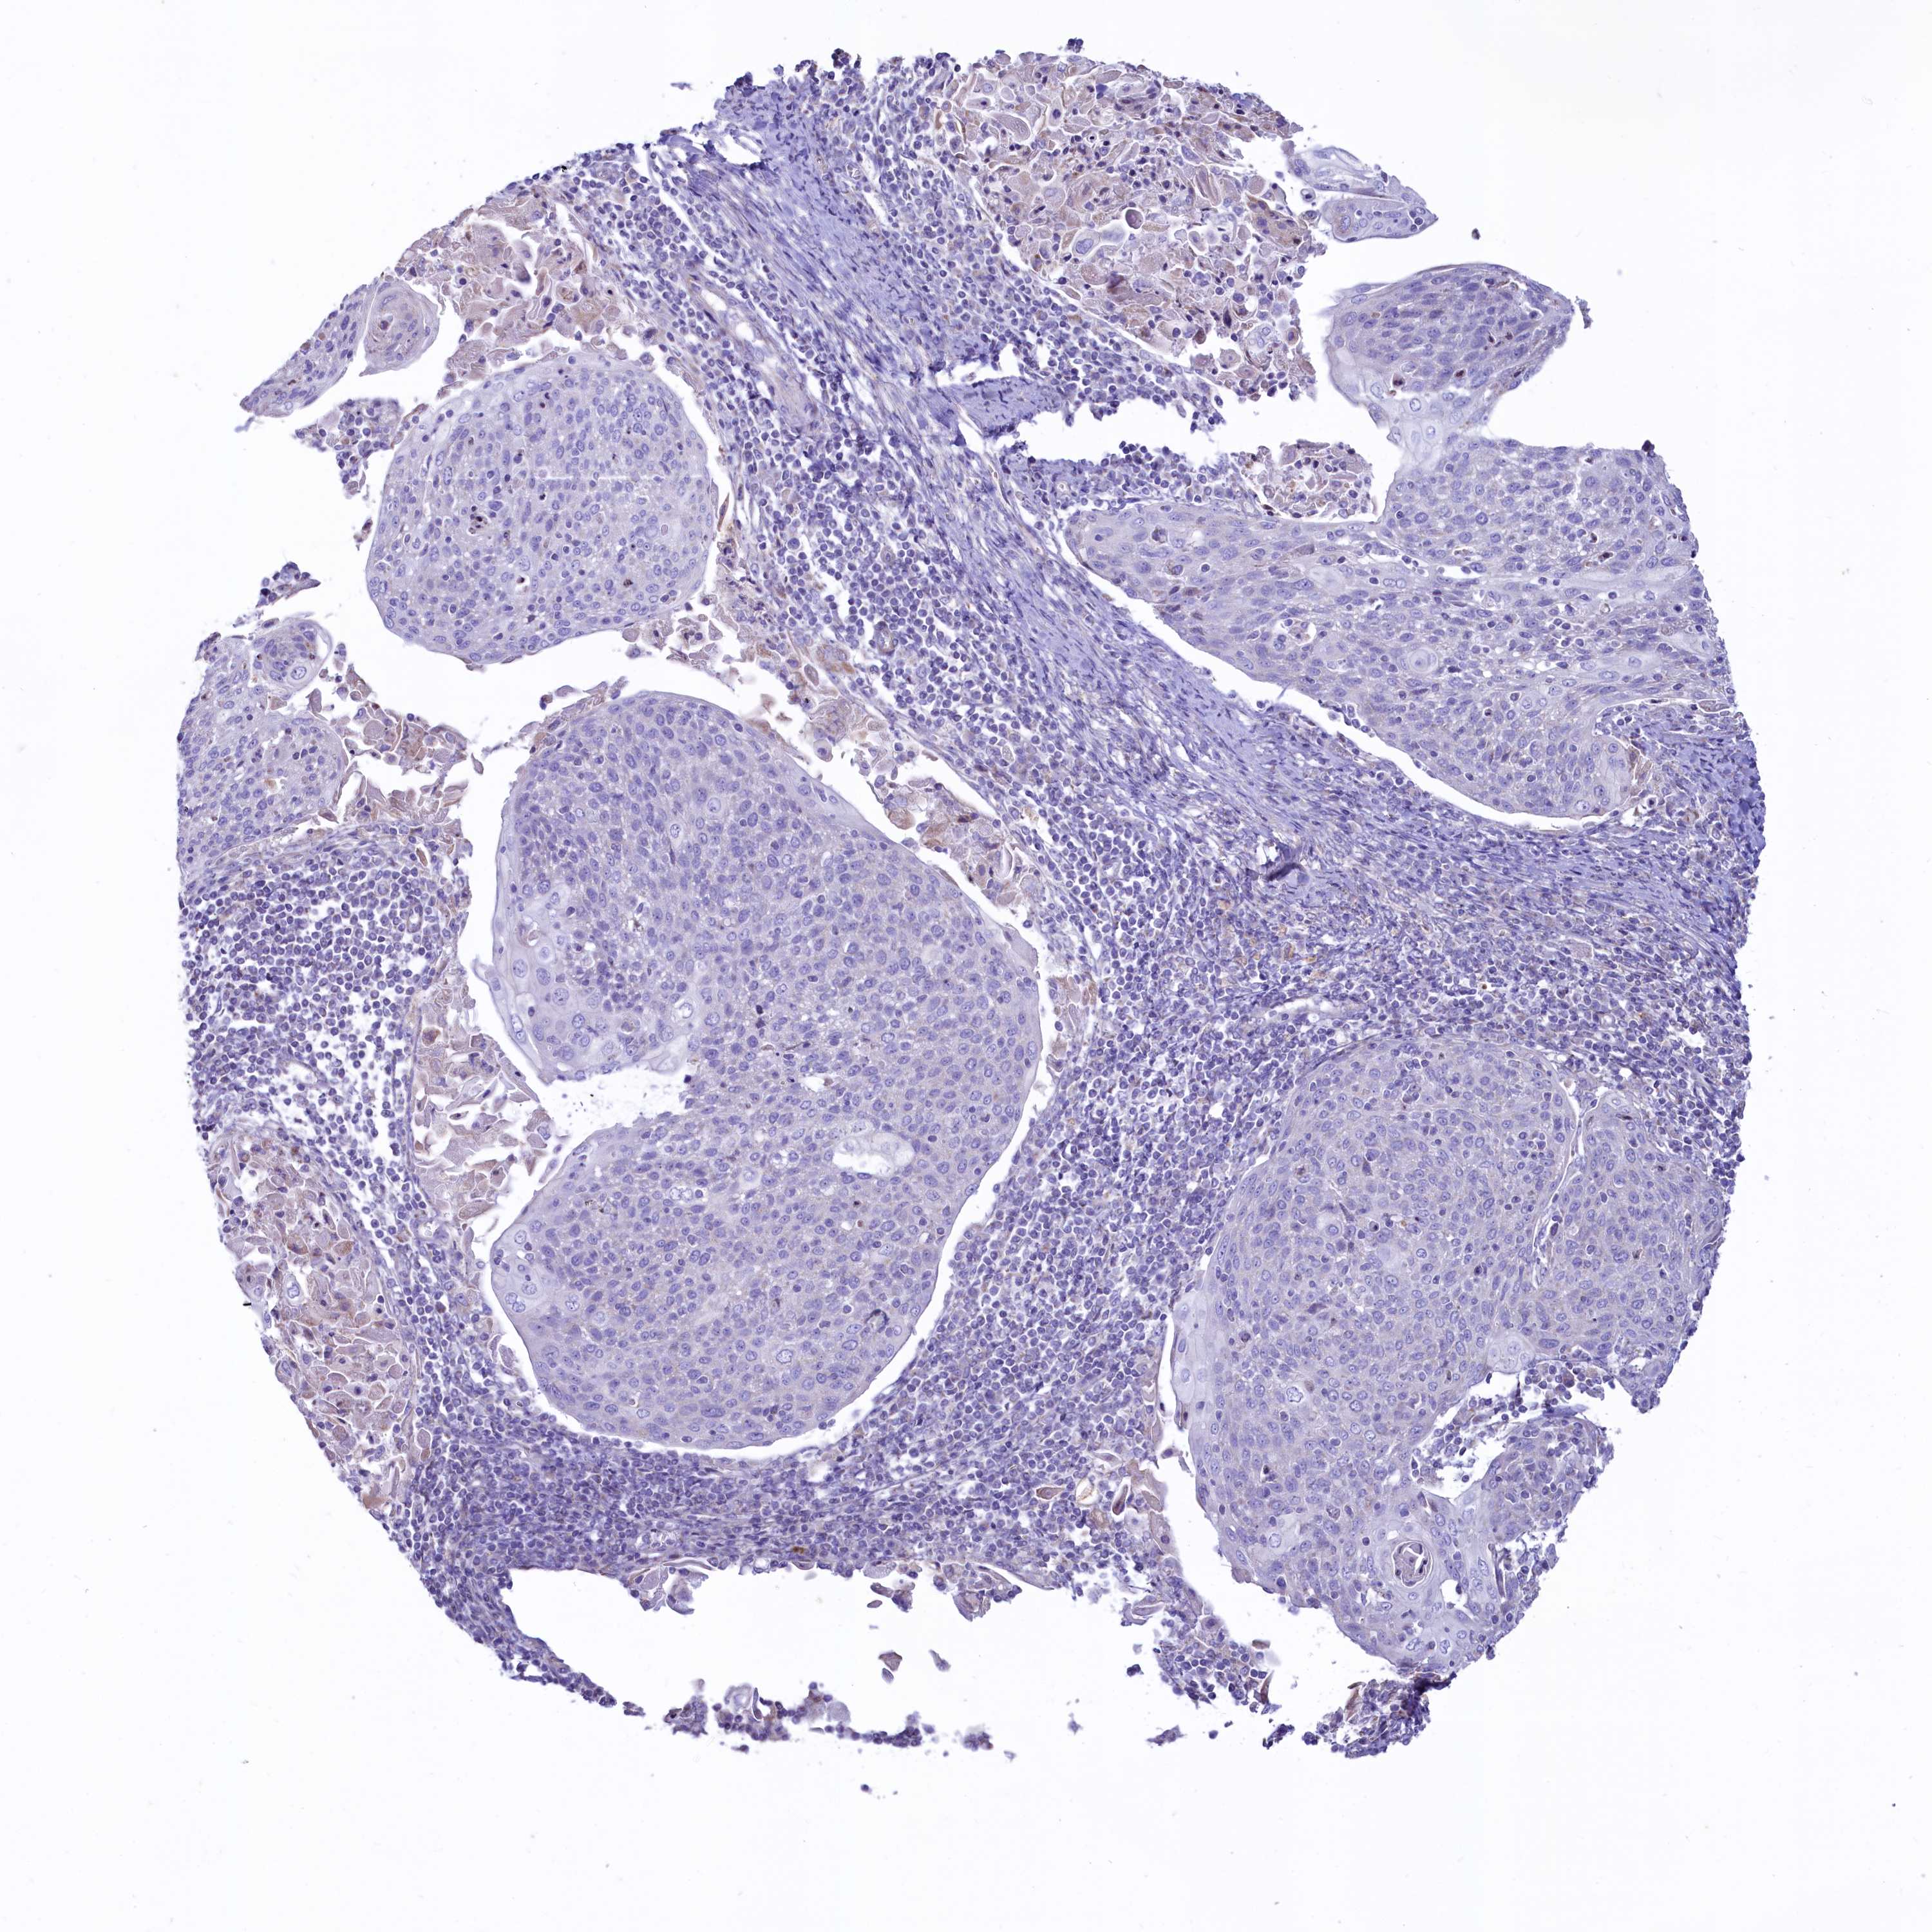

CERVICAL CANCER - Protein expressioni

A mouse-over function shows sample information and annotation data. Click on an image to view it in a full screen mode. Samples can be filtered based on level of antibody staining by selecting one or several of the following categories: high, medium, low and not detected. The assay and annotation is described here.

Note that samples used for immunohistochemistry by the Human Protein Atlas do not correspond to samples in the TCGA dataset.

Antibody stainingi

Antibody staining in the annotated cell types in the current human tissue is reported as not detected, low, medium, or high, based on conventional immunohistochemistry profiling in selected tissues. This score is based on the combination of the staining intensity and fraction of stained cells.

Each image is clickable and will lead to virtual microscopy that enables deeper exploration of all samples and also displays staining intensity scores, fraction scores and subcellular localization as well as patient and tissue information for each sample.

Antibody HPA040401

Antibody HPA043921

Staining

High

Medium

Low

Not detected

Intensity

Strong

Moderate

Weak

Negative

Quantity

>75%

75%-25%

<25%

None

Location

Nuclear

Cytoplasmic/membranous

Cytoplasmic/membranous,nuclear

Squamous cell carcinoma, NOS

Adenocarcinoma, NOS